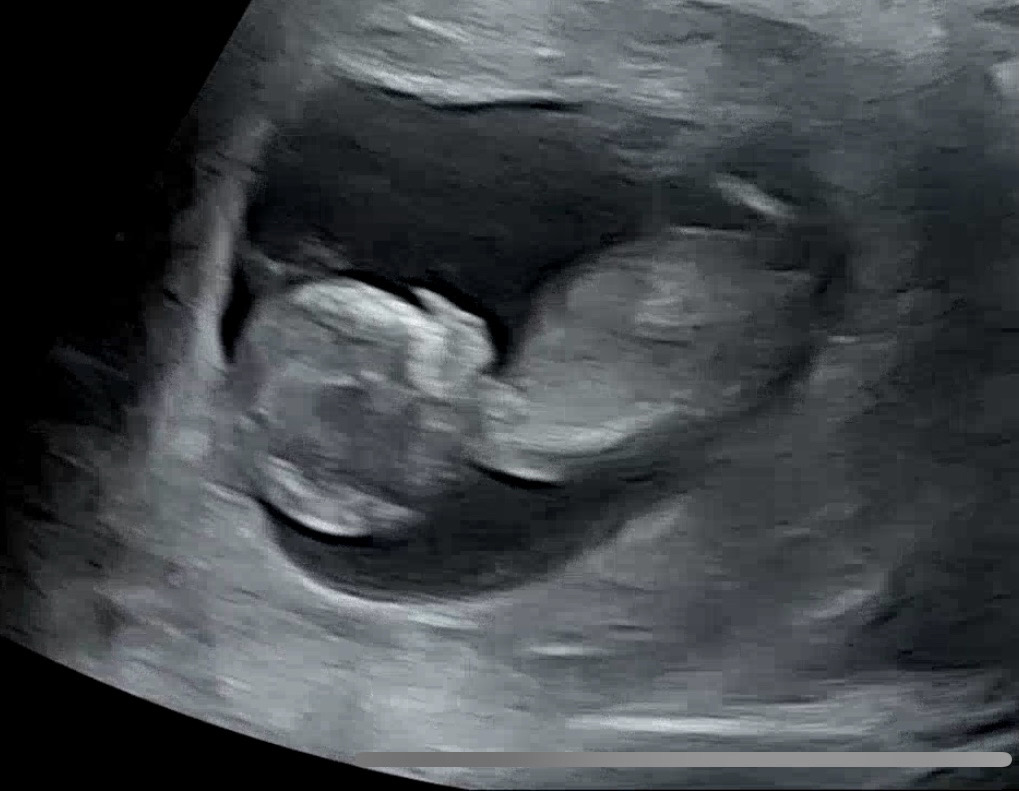

저 11주5일차에 입덧 벗어나고 있어요!!!! 입덧으로 힘든 예비맘들 희망을 가지세요!!!!! 입덧 6주차부터 장난아니었어요 명치에 낑깡 낀거마냥 답답하고 울렁거리고 매일 토하면서 11주까지 보냈습니다ㅠㅠㅠ하루에 10번이상 토할때도 많았어요ㅠㅠ진짜 입덧약 최대치로 먹어도 듣지도 않았답니다..수액도 계속 맞고요 토를 너무해서 식도가 상처가 낫는지 피까지 토하고 난리도 아니였어요 피토한 날에는 음식물 삼킬때마다 쓰라려서 죽만먹구요ㅠㅠㅠ위염약 처방받았슴다😭카페에서 일하다가 간헐적 토덧때문에 일도 그만두고 정말 산송장 그 잡채... 근데 11주 2일차부터 서서히 토를 안하더니 오늘은 입덧하나도 안해요!! 약도 서서히 줄이고 있는데 멀쩡하답니다 정말 12주의 기적이 오려나봐요 오늘 아짱이 1차 기형아 검사도 무사통과했습니다🫶이제는 정말 사람처럼 꼬물꼬물거리는 아짱이 보니까 정말 힘들었던게 다 보상이 되네요❤️ 입덧 체덧 토덧 양치덧으로 힘든 모든 8월베동맘들 힘내세요👊🏻입덧도 끝이 옵니다!!!만세!!